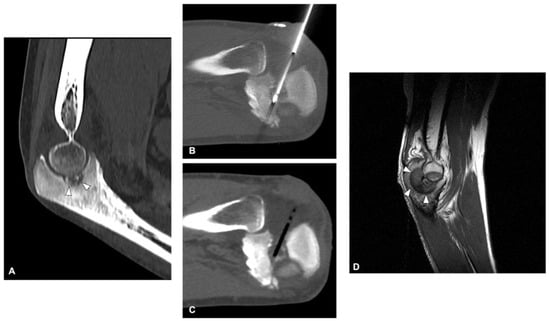

4.2. Osteoblastoma

- Cazzato, R.L.; Auloge, P.; Dalili, D.; DE Marini, P.; Di Marco, A.; Garnon, J.; Gangi, A. Percutaneous Image-Guided Cryoablation of Osteoblastoma. Am. J. Roentgenol. 2019, 213, 1157–1162. [Google Scholar] [CrossRef]